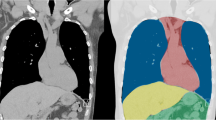

Advances in the field of artificial intelligence (AI), and in computing in the past decade, have made possible artificial neural networks that can “learn” to perform tasks previously reserved exclusively for humans. AI-enabled applications are already being deployed in radiology to assist in the detection and classification of diseases. The emergency department (ED), where timely and accurate diagnosis is critical, is an area of great interest for application of AI-driven solutions. AI algorithms offer great promise for addressing the challenges posed by increasing imaging volumes, increasing case complexity, and the need for rapid turnaround of results. Many products have already received US FDA clearance for clinical use. This chapter provides an introduction to key AI concepts, explores applications of AI in emergency radiology, and considers implications that AI will have for the field.